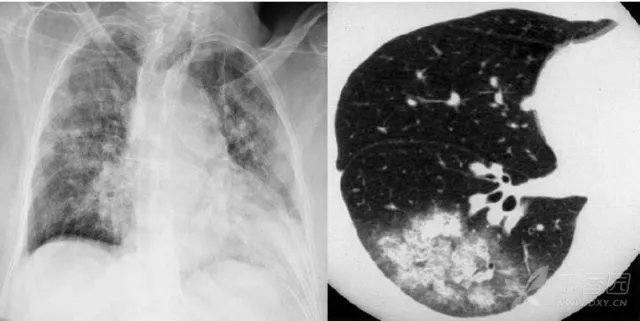

大葉性肺炎胸部影像

簡單來講,肺炎出現(xiàn)較大的病灶,局限在一個(gè)肺葉,就叫大葉性肺炎。大葉性肺炎也叫肺泡性肺炎,這是因?yàn)榇笕~性肺炎的炎性滲出主要發(fā)生在肺泡。細(xì)菌、病毒、真菌、以及肺炎支原體等非典型病原體都可以引起大葉性肺炎。